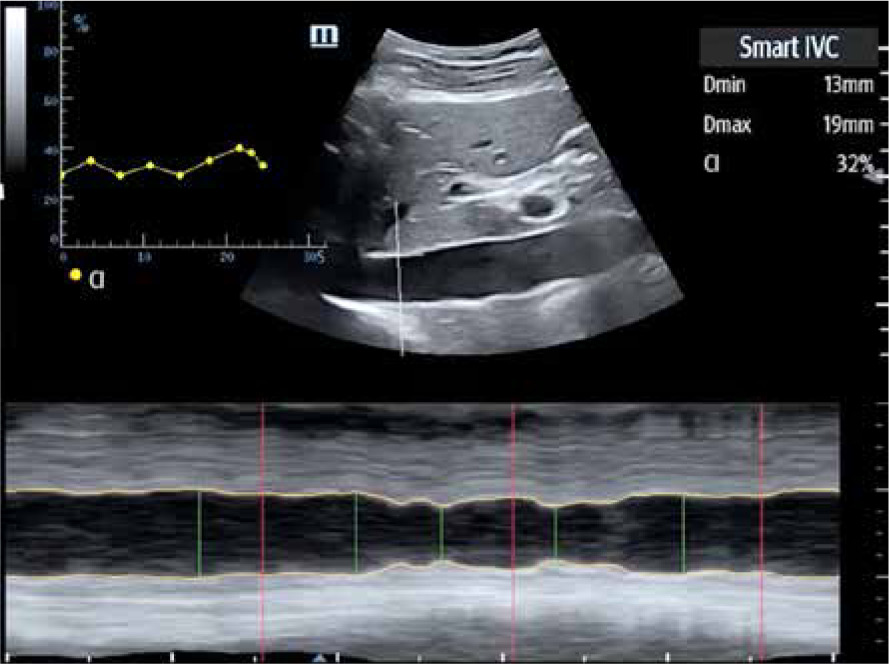

– SmartIVC (Mindray) or AUTO IVC (GE) provides automatic measurement of the inferior vena cava, which helps to estimate susceptibility to fluid therapy. A condition to obtain a trend graph documenting changes in the collapsibility index and the diameter index (DI) is projection of the inferior vena cava along the long axis on the level of the xiphoid process. As soon as an image like that presented in Figure 5 is obtained, along with the fragment of the right atrial orifice, it is possible to click on the SmartIVC icon to start the automatic measurement. The system will automatically present collapsibility index and DI values in real time along with the quotient of the 2 parameters expressed as the collapsibility percentage.

FIGURE 5

Graphic presentation of Smart B-Line software – automatic measurement of the inferior vena cava (author’s own source)

It should be noted, however, that each measurement may be flawed due to mobility characteristics of the inferior vena cava, which may result in measurement of one of the chords and not the actual diameter of the vessel.